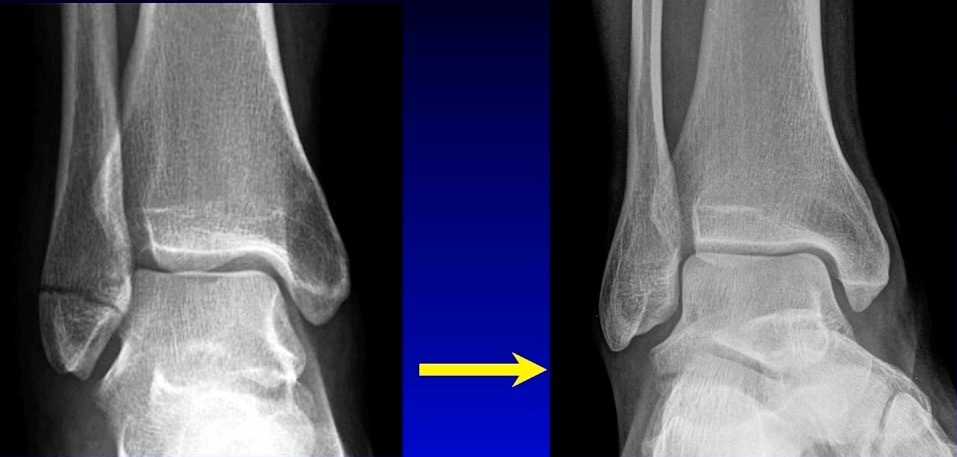

There’s much controversy in terms of should we wait or should we allow acute weight bearing following fixation of an unstable ankle fracture. Traditionally, patients were kept non-weightbearing for 6-12 weeks in some kind of cast or a boot. Nowadays, more contemporary approach is to allow earlier mobilization and protected weight bearing. Additionally, there’s many differences between North American and European schools of thought. When I give this talk to Europeans, they say “yeah we start immediate weight bearing all the time, that’s the standard.” But it’s certainly not the view in North America. I still see patients that have a beautiful x-ray with everything fixed and they’re kept in a cast for two months, which potentially defeats the whole point of surgical fixation. The benefit of surgery is to allow early mobilization and protected weight bearing. This practice can accelerate your patient’s return to work and return to life. However, nobody wants to see this x-ray in their clinic, especially with the staples still in (Figure 3).

This example is the fear that drives behavior amongst most orthopaedic surgeons who do not allow patients to move early.